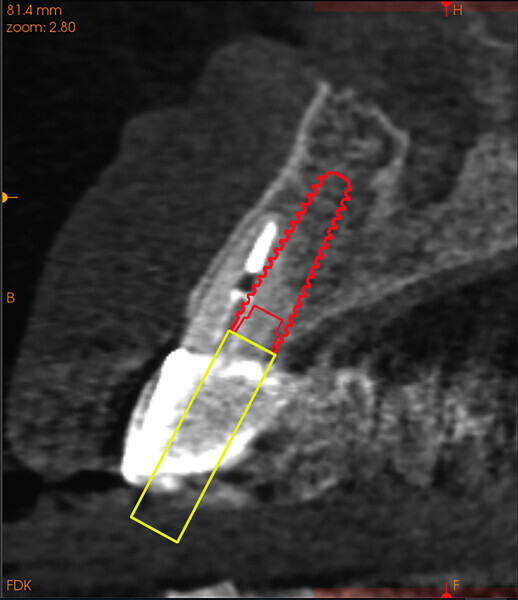

Fig. 3a: Planning the initial drill path using a custom implant design (red) to match the

diameter of the initial drill to reach the tooth apex. The abutment projection is shown in yellow.

3b: The simulated implant within the Triangle of Bone (red), placed to avoid the root fragment seen in yellow (white arrows).